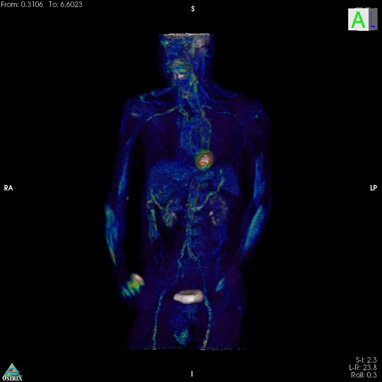

Si può manifestare una cefalea anche in altre malattie vascolari intracraniche, senza che vi siano dei sanguinamenti.

Anche in questi casi deve essere comprovaro il nesso temporale e causale. La sede del dolore varia a seconda della patologia vascolare di cui si tratta, che sia essa un'aneurisma, ovvero una malformazione arterovenosa, una fistola arerovenosa, eccetera.

Le caratteristiche possono essere acute rombo di tuono come nell'aneurisma, aggravate dalle manovre di Valsalva e pulsanti come nella fistola arterovenosa, ovvero persistenti come nella malformazione arterovenosa.

In ogni casi è necessario e diagnostico effettuare una valutazione neuroradiologica appropriata ed eventualmente altre indagini neurologiche ove appropriato.